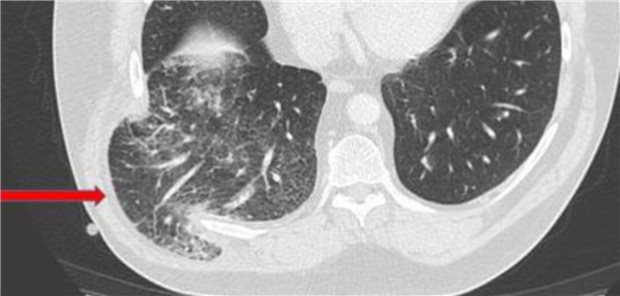

Ein stark übergewichtiger Patient mit schwerer COPD klagt nach einem heftigen Hustenanfall über massive, rechtsseitige Thoraxschmerzen und Hämoptoe. Die Computertomografie bringt des Rätsels Lösung. Ein Fallbericht.